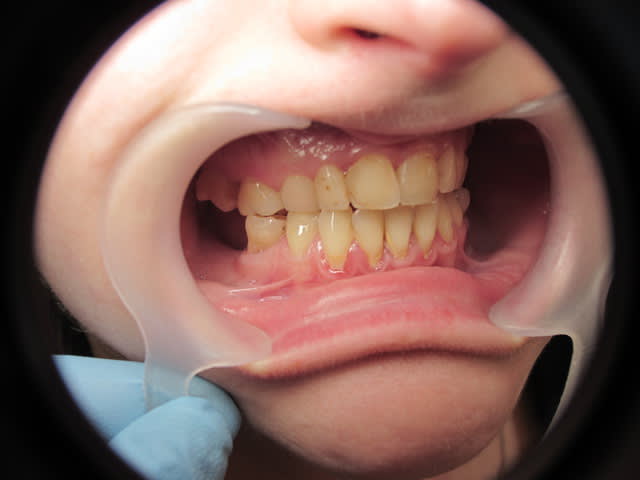

Patiente de 33 ans, questionnaire de santé RAS, demande esthétique. Elle souhaiterait que ses dents soient "davantage visibles" lors du sourire. Les dents absentes sont dues à des agénésies.

Il y a agénésies de 14-15 et 24-25, de 35 et 45 (restent 75 et 85), des molaires du bas. En haut j'avoue que je ne sais pas si ce sont des molaires de lait ou définitives...

Sa mère et sa soeur présentent les mêmes agénésies ou presque.